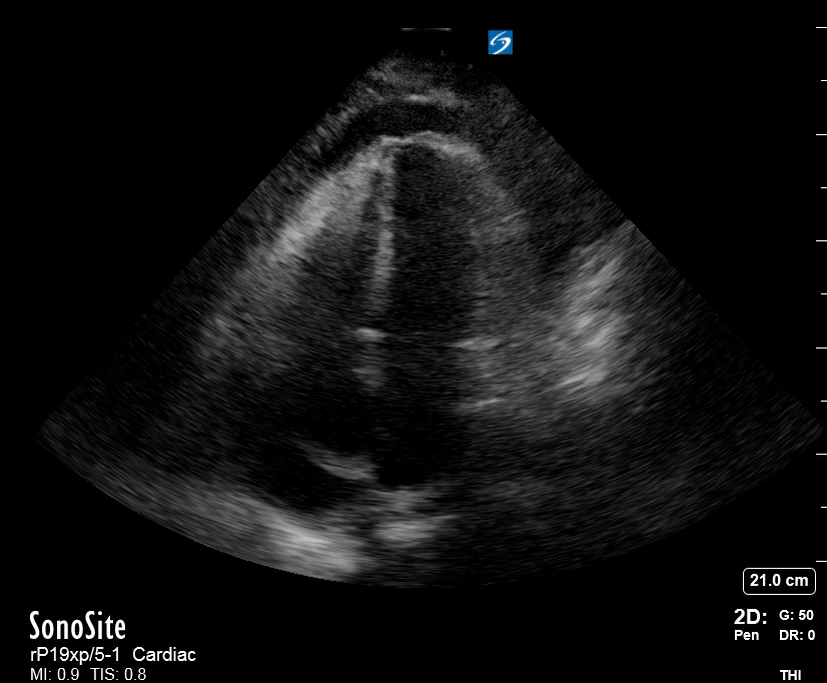

THE VIEWS

The A4C view provides an accurate chamber size comparison. However, achieving a proper A4C view (avoiding foreshortening or ballooning, and visualising the four chambers with a vertically oriented interventricular septum) can be a challenging exercise of image acquisition. Additionally, the PSAX view at the level of the papillary muscles shows both LV and RV side by side and is useful to assess function and size. When RV pressure is high, the septum will be pushed and flattened towards the LV, resulting in the characteristic “D-shaped” LV or “D sign”.

PITFALLS

When comparing size, beware of correct image acquisition, as oblique planes lead to misinterpreting the RV:LV ratio. For apical views be sure to slide the probe sufficiently laterally on the chest wall so that it lies over the true apex. Also, be sure to obtain a real horizontal plane, avoiding foreshortening (ballooning). For the PLAX view it is useful to fan through the heart’s long axis, making sure that LV visualization is maximized relative to the RV. Furthermore, an understanding of probe placement and marker orientation conventions is fundamental. If inadvertently scanning in reverse orientation, the normally larger LV could be mistaken for an abnormally enlarged RV.